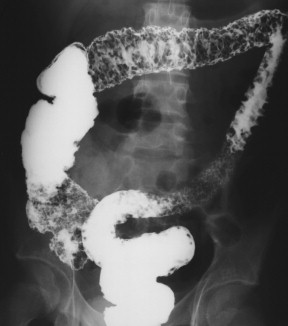

The imaging features depend on the stage of the disease ( Table 5-2 ), and many of these features are shared by Crohn disease ( Table 5-3 ). They can sometimes be identified by plain abdominal radiography as thickened haustra, particularly when caused by a pancolitis ( Fig. 5-5 ). Severe disease can almost certainly be recognized on plain radiography as can toxic megacolon, with marked colonic distention resulting from ileus ( Fig. 5-6 ) and wall and mucosal thickening ( Fig. 5-7 ). The wall thickening is sometimes referred to as “thumb-printing” because of the polypoid soft tissue nature of the mucosal edema and thickening. BE demonstrates typical features but has largely been replaced by optical colonoscopy for diagnosis. When BE is performed, the features depend on the severity and acuity of disease. In acute disease a variable length of colon (starting in the rectum) shows a granular mucosal pattern representing edema and ulcer formation, sometimes of the whole colon ( Fig. 5-8 ), which may also affect the last few centimeters of the terminal ileum (“backwash ileitis”) ( Fig. 5-9 ). “Collar-button ulcer” formation has been described, which represents acute ulceration of the colon with submucosal extension ( Fig. 5-10 ), with further ulceration prevented by the relatively impermeable bowel wall. This sign is three times as common in UC as in Crohn disease. Pseudopolyp formation, which can also be recognized in Crohn disease, can occur with more chronic disease and represents areas of reparative mucosa between areas of ulceration ( Fig. 5-11 ). As the disease progresses, the affected length of colon becomes featureless and shortened, termed “lead piping” ( Fig. 5-12 ).

Figure 5-8, BE in a 23-year-old man with pancolitic granular appearance due to acute ulceration from ulcerative colitis.